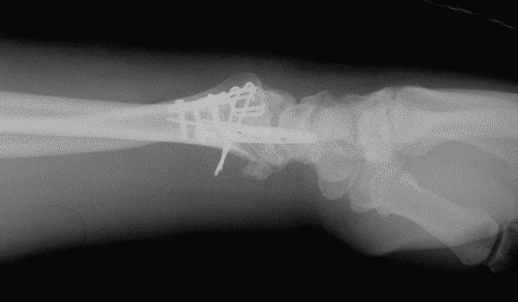

Case3 Postop